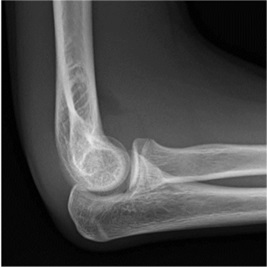

Anterior fat pad elevated off anterior surface of humerus = joint effusion |

|